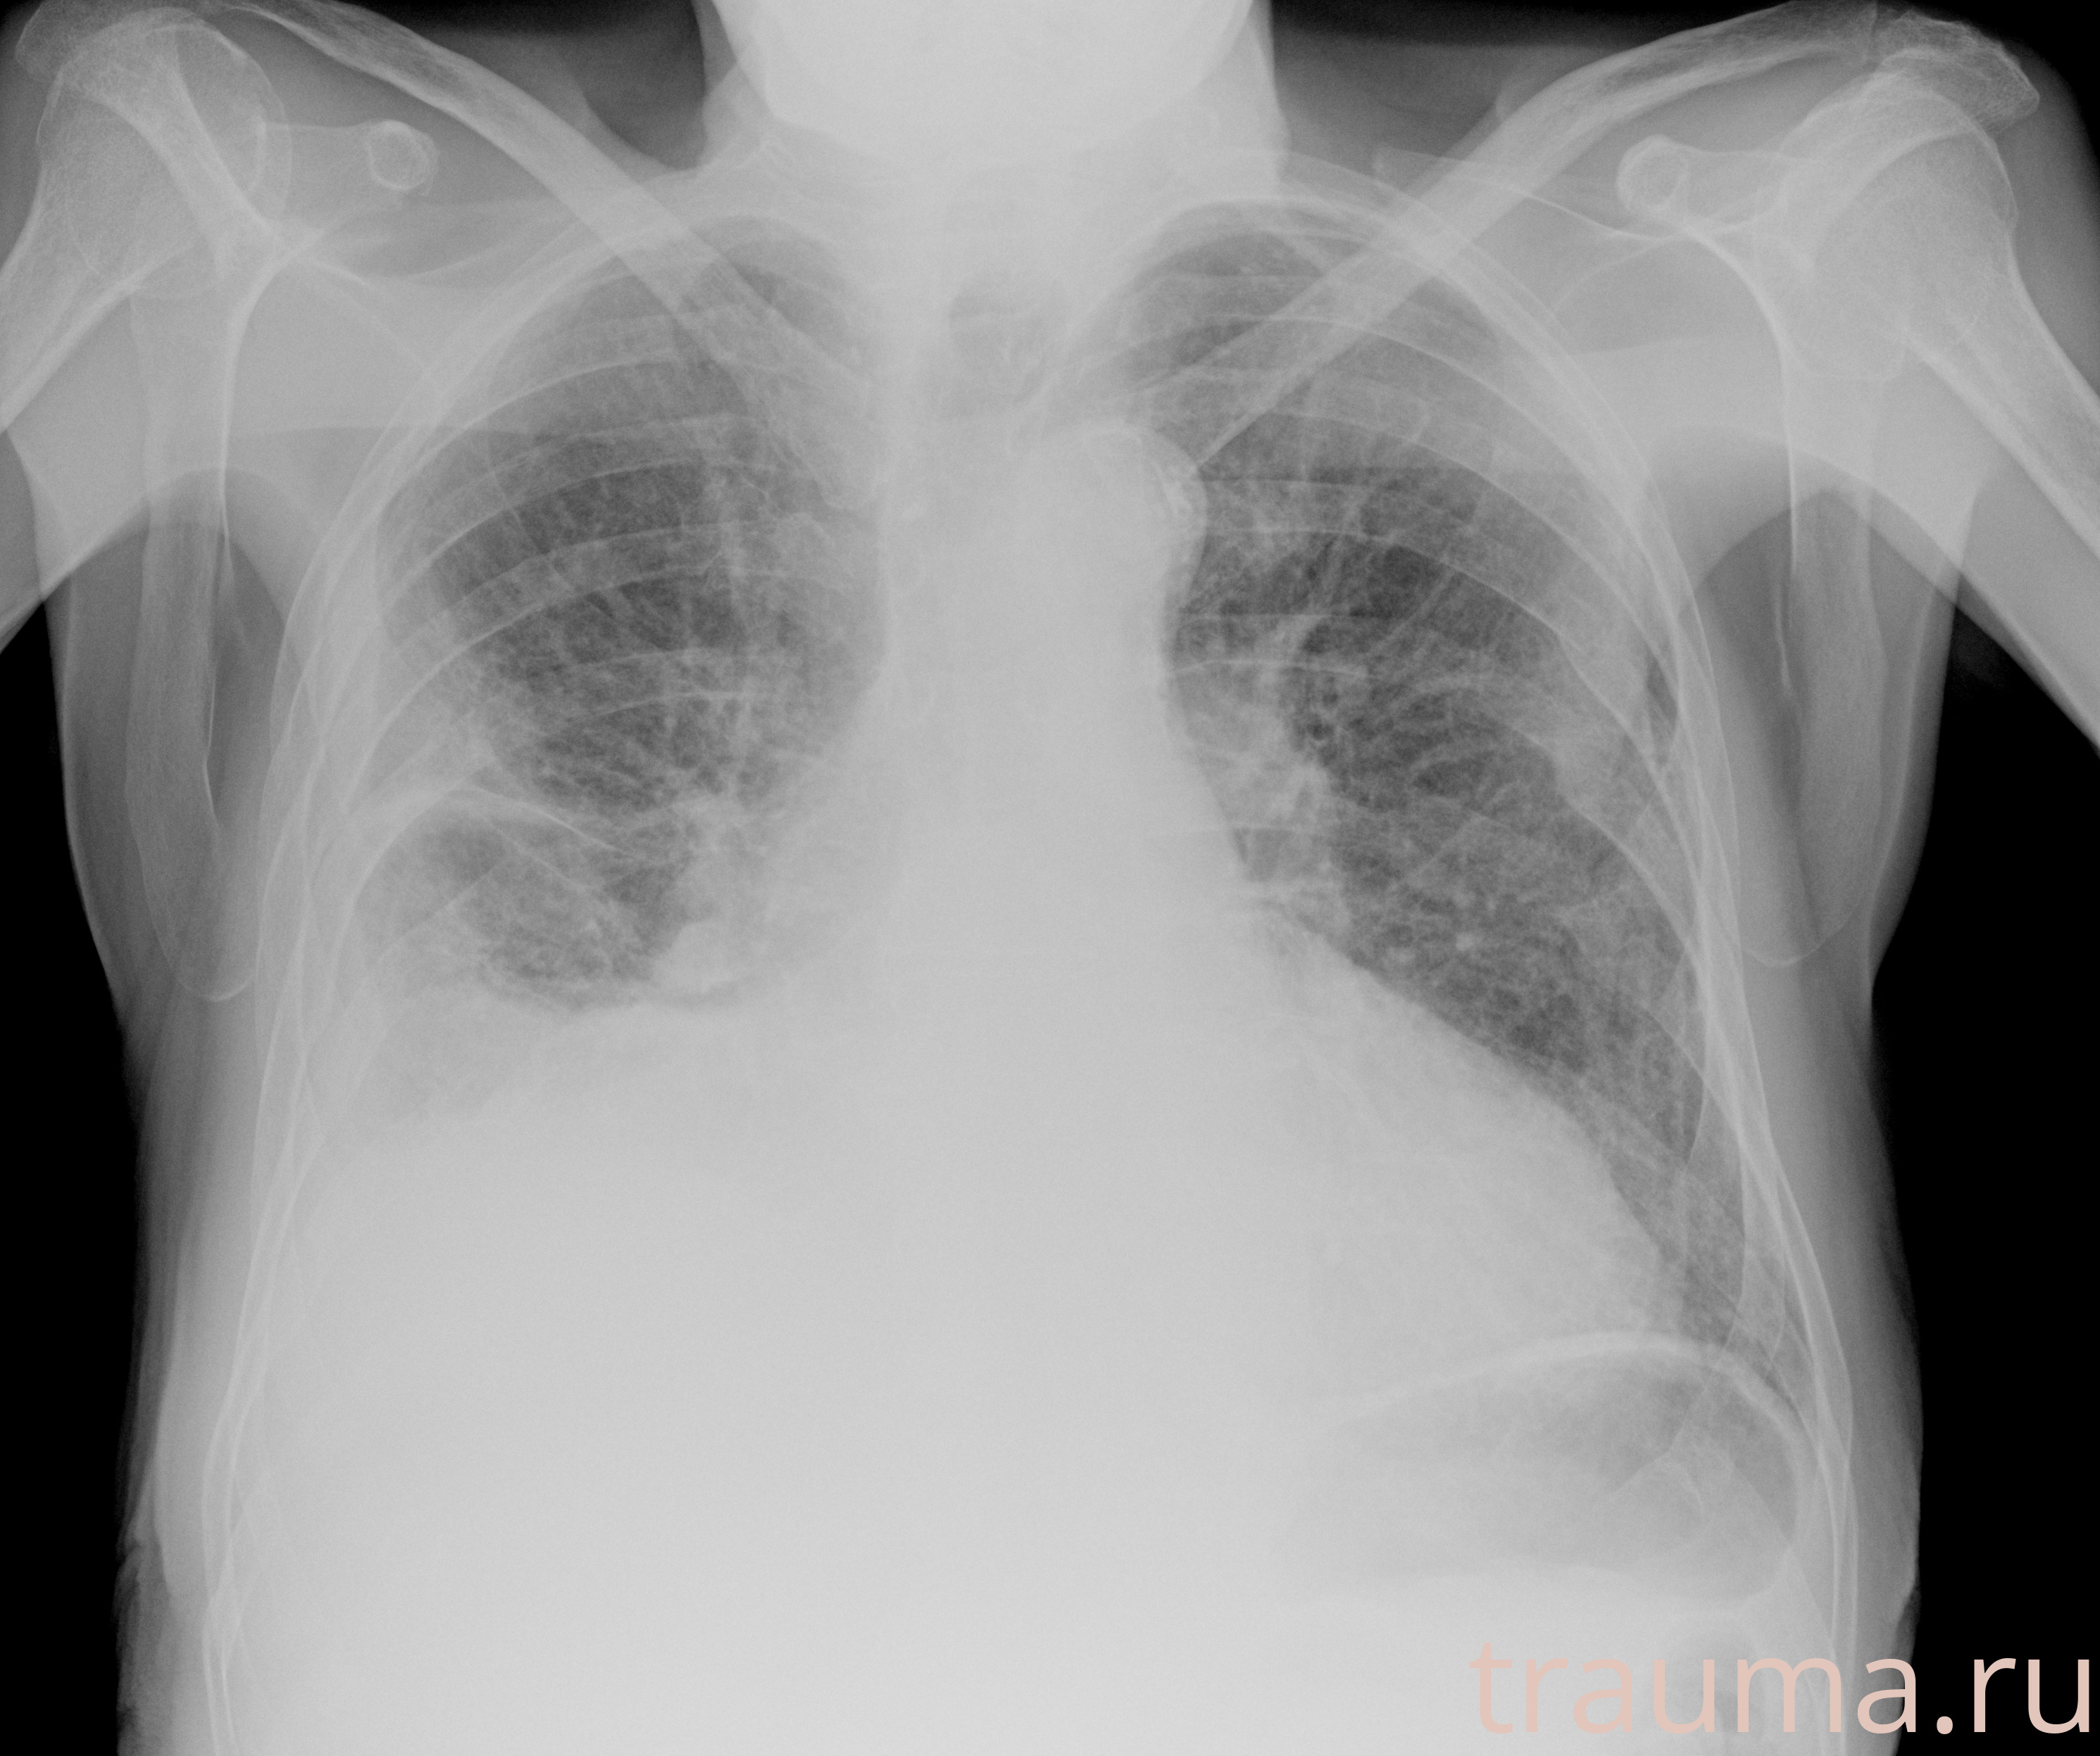

Рентген на дому: по вашему адресу приезжает врач-рентгенолог, травматолог-ортопед с мобильным рентгеновским аппаратом, проводит диагностику травмы или заболевания, делает необходимые рентгенограммы, дает рекомендации по дальнейшему лечению. Получить качественные снимки в домашних условиях возможно благодаря уникальной методике, разработанной МосРентген Центром для института  Склифосовского

при переломе шейки бедра и пневмонии от компании МосРентген Центр - партнера Института имени Склифосовского